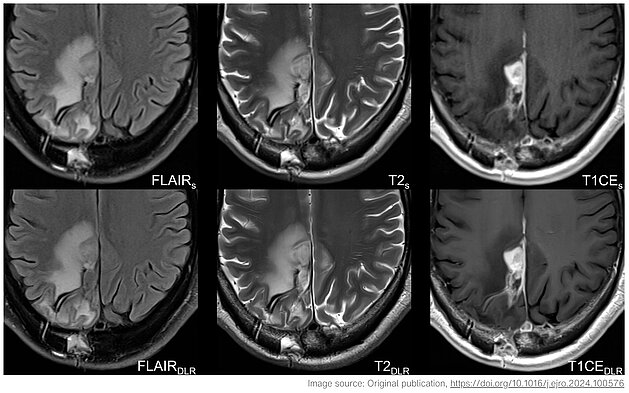

Postoperative Hirntumor-MRT mit Vergleich von TGSE-BLADE und RESOLVE DWI zur Darstellung von Artefakten und Resektionsareal

Eine aktuelle Studie im European Journal of Radiology vergleicht TGSE-BLADE DWI mit RESOLVE DWI in der postoperativen Hirntumor-Bildgebung. TGSE-BLADE zeigt signifikant weniger Verzerrungen und Artefakte durch intrakranielle Luft und ermöglicht eine präzisere Beurteilung ischämischer Veränderungen. Die Ergebnisse sprechen für TGSE-BLADE als robuste Alternative in der klinischen Routine.

Universitätsklinikum Tübingen: Verbesserung der postoperativen MRT bei Hirntumoren: TGSE-BLADE vs. RESOLVE DWI

Frühe MRT-Untersuchungen sind entscheidend für Patient:innen, die sich einer Hirntumorresektion unterzogen haben, um den Erfolg der Operation zu…